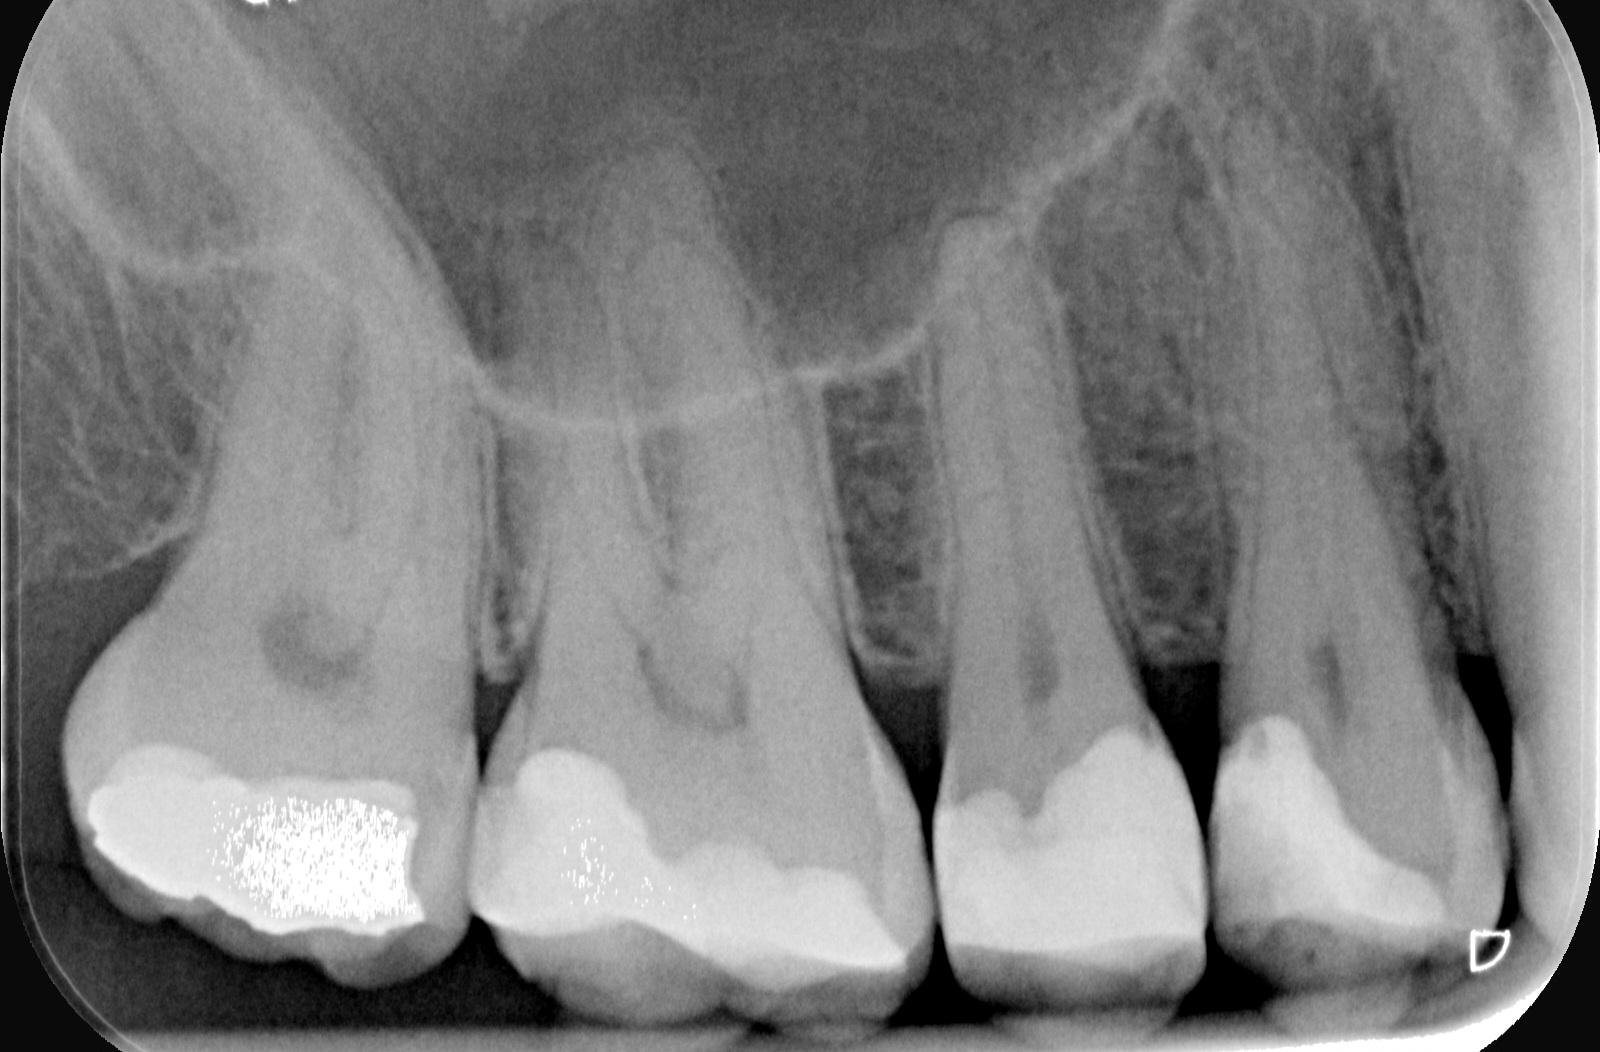

In der Zahnregion 1.4-1.7 habe ich Probleme mit freiliegenden Zahnhälsen sowie Füllungen. Die Zahnregiin ist empfindlich, manchmal auch ein Ziehen. Auf einen konkreten Zahn kann ich es nicht beziehen. Mein Hauszahnarzt kann nicht genau sagen, ob dies von den freiliegenden Zahnhälsen kommt oder ob es noch andere Probleme gibt. Sehen Sie Auffälligkeiten im Röntgen? Für mich sieht es aus, als wäre bei dem 4er Zahn ein dunkler Schatten um den Füllungsrand. Ist dies nur der Kleber der Füllung oder eine erneute Karies? Gibt es sonst aus Ihrer Sicht Auffälligkeiten auf dem Bild?